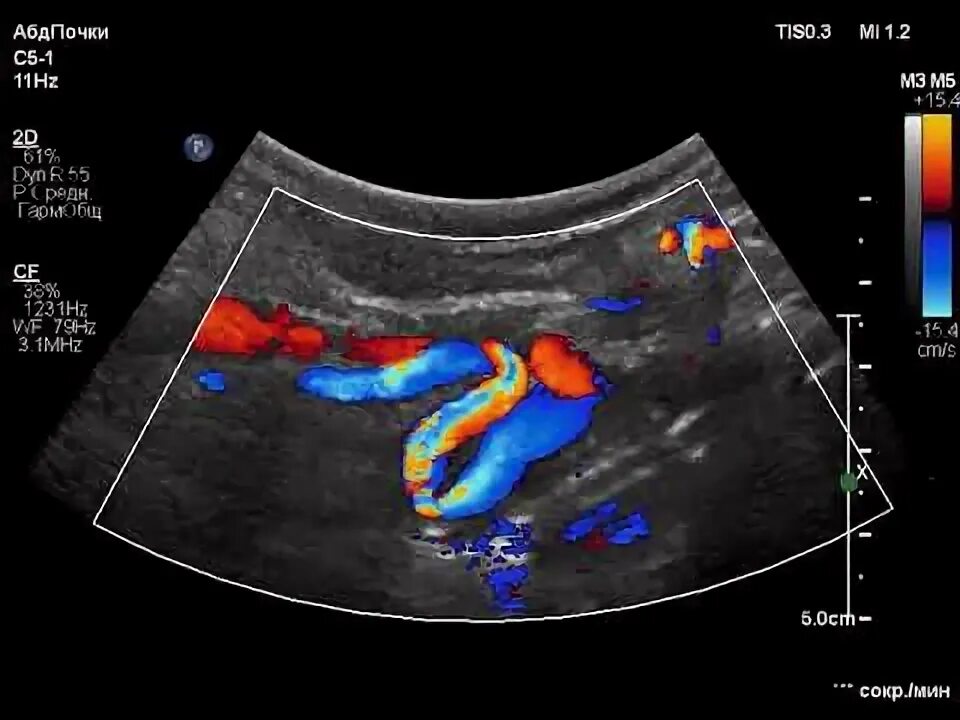

S образный изгиб артерии